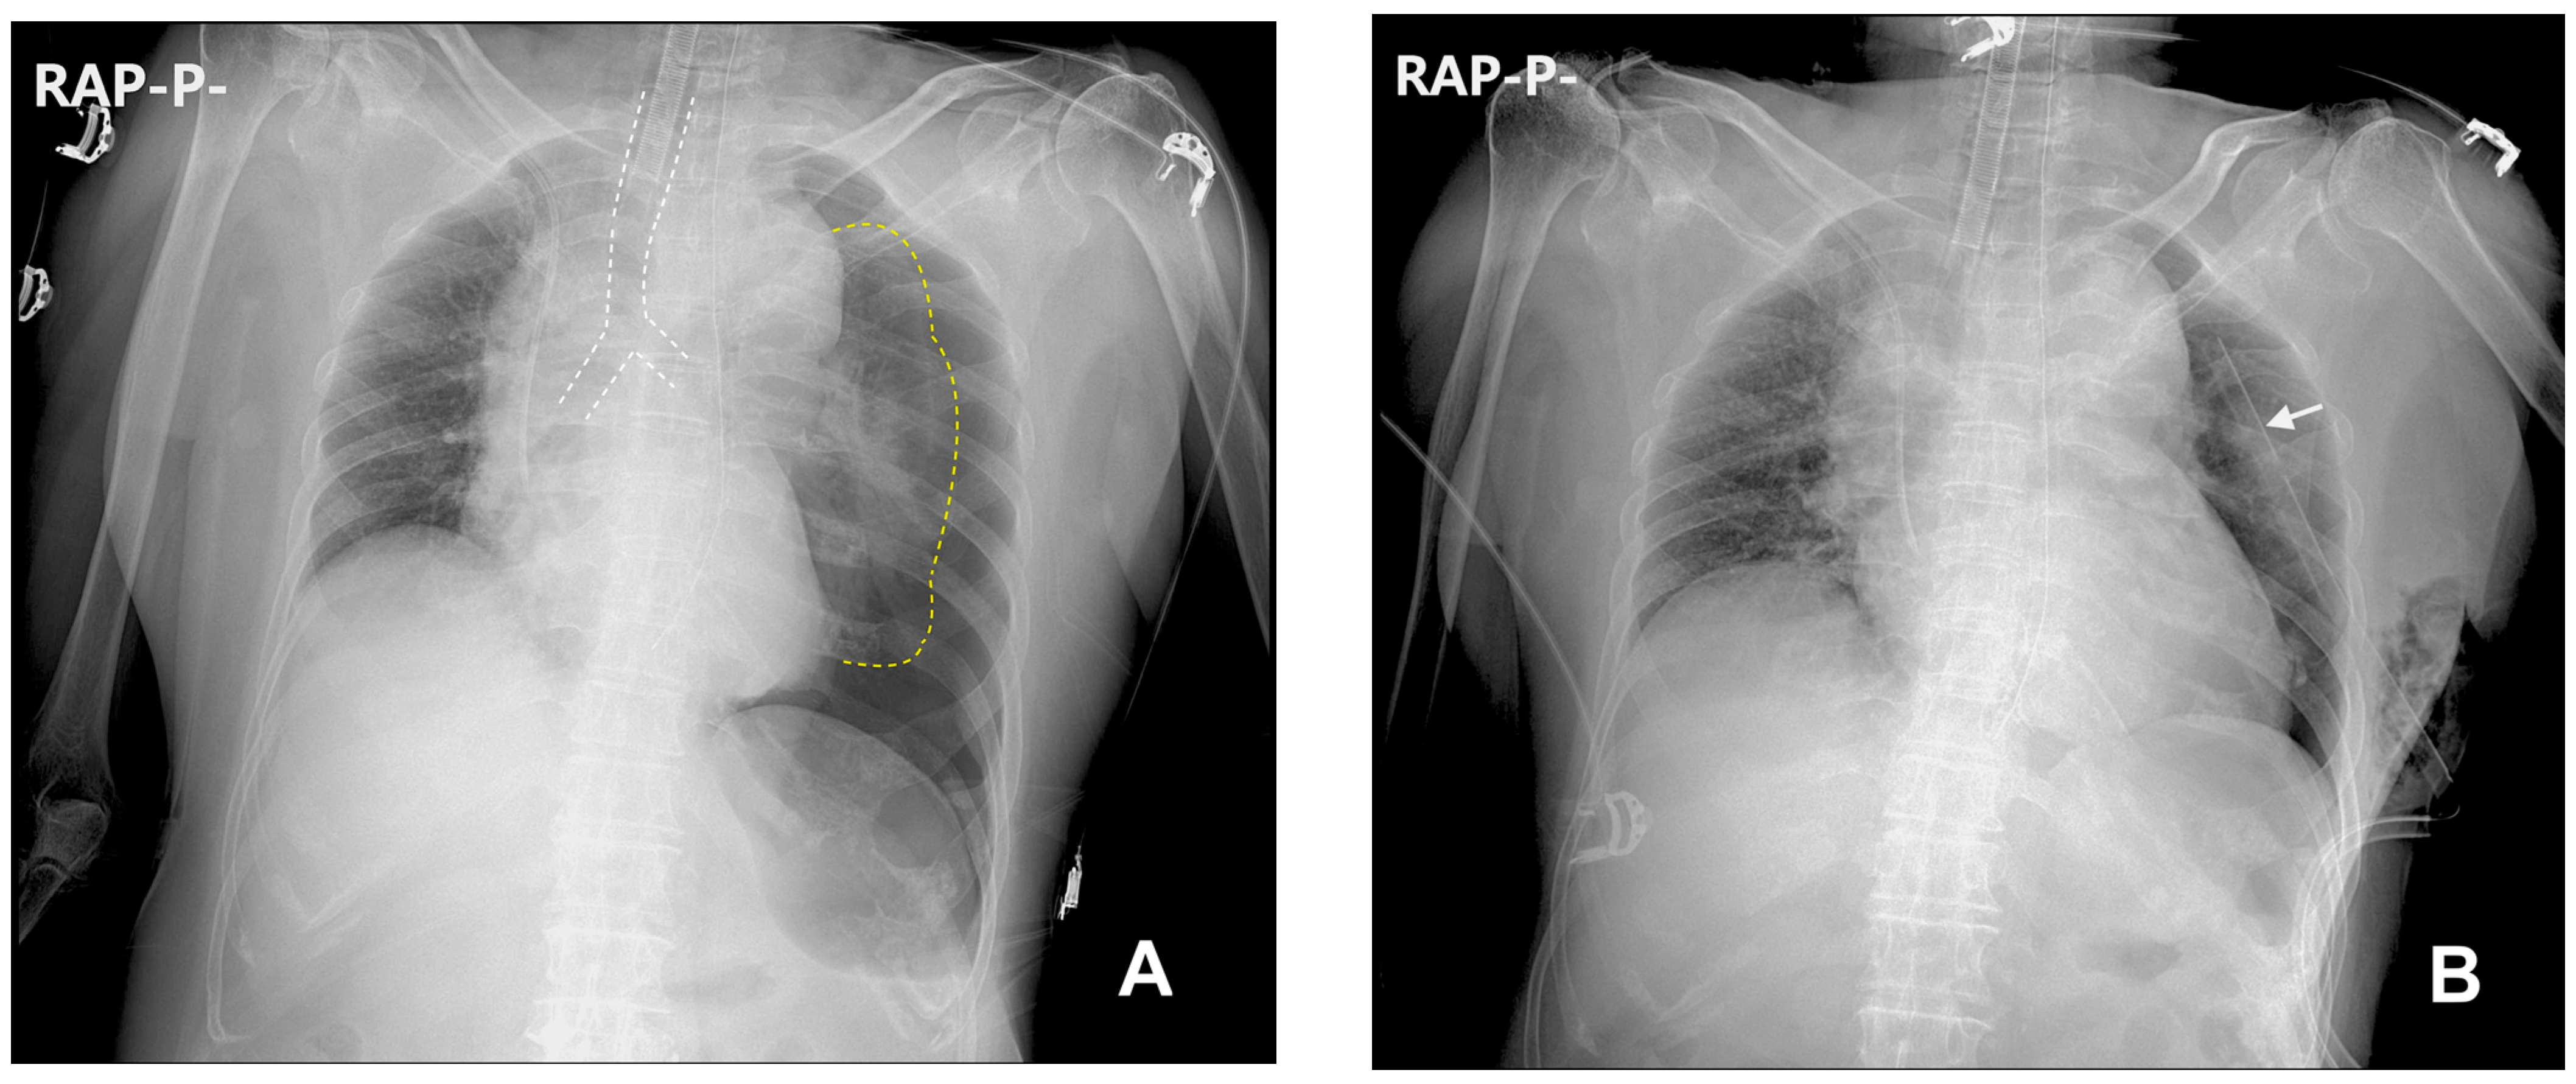

2. Case Description